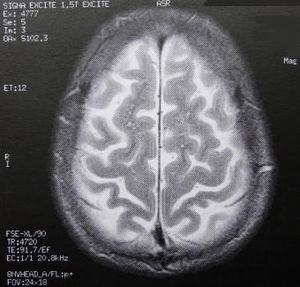

Gehirn-Scan: Forscher untersuchen Belohnungsprozesse (Foto: pixelio.de, Schütz) |

Die Wissenschaftler untersuchen sowohl Patienten mit Schizophrenie als auch gesunde Personen mit unterschiedlichen Ausprägungsgraden verschiedener Persönlichkeitseigenschaften. Untersucht wurde im Magnetresonanztomographen. Ursprüngliche waren die Forschungen bislang auf Tiere beschränkt. Mithilfe der funktionellen Kernspintomographie ist es relativ unaufwändig, die Hirnaktivierung während einer Belohnung beim Menschen zu messen. In diesen Studien wurden eine Reihe von Regionen identifiziert, welche verschiedene Rollen bei der Verarbeitung einer Belohnung einnehmen.